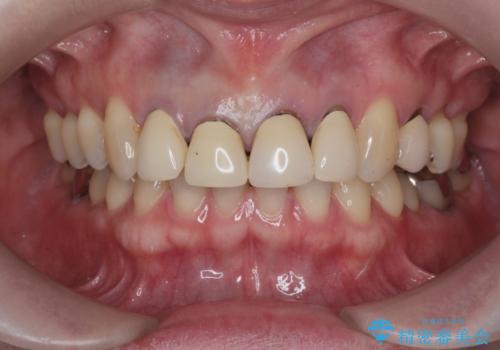

- 「黒ずみの前立つ前歯をやりかえ、きれいにしたい。」と希望され来院されました。

金属色の目立つ前装冠を除去し、発生していた小さな虫歯を丁寧に全て除去しジルコニアセラミッククラウンで審美的な前歯となるような治療を計画します。

金属を用いないジルコニアセラミッククラウンは透明感の再現性に優れ、審美性と自然な仕上がりの両立を期待することができます。